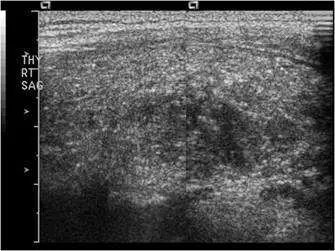

⼀位女性病患右側甲 狀腺及右下邊脖⼦淋巴腺無痛性腫⼤,其右側甲狀腺灰階及彩⾊杜⼘勒超⾳波檢查如圖,最可能的診斷 為何?

本題考慮一位女性病患出現右側甲狀腺及右下頸部淋巴結無痛性腫大,提供右側甲狀腺的灰階(B-mode)及彩色杜卜勒(color Doppler)超音波影像,要求判斷最可能的診斷。無痛性甲狀腺腫塊合併頸部淋巴結腫大,配合超音波影像特徵,是甲狀腺乳突狀癌(papillary thyroid carcinoma, PTC)的典型臨床表現。

本題共提供三張超音波影像(THY RT TR/SAG 標示,即右側甲狀腺横切及縱切面):

- 右側甲狀腺整體體積略增大,內部回音不均勻。